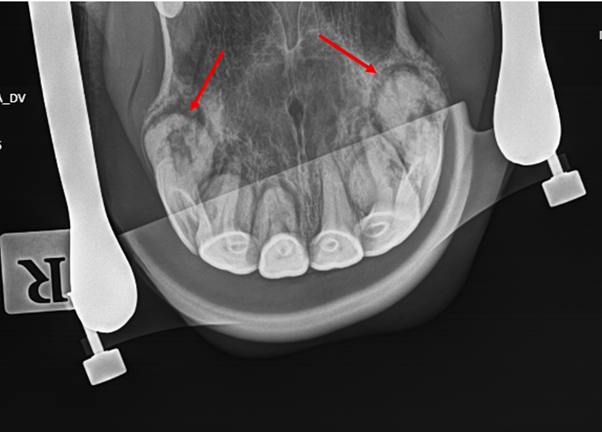

Image showing the mostly normal external appearance of the incisors

EORTH is a progressive dental condition affecting the incisors, most commonly in middle-aged to older horses. One of the challenges with this disease is that the visible part of the teeth can appear relatively normal, while significant and painful changes are occurring below the gumline at the level of the tooth roots.

Radiograph showing the severity of disease of the gelding’s incisor roots (arrows)

Incisors after removal showing severely diseased and thickened roots (arrows)